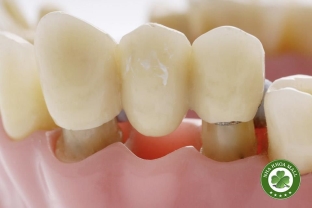

• Nha khoa thẩm mỹ: Tẩy trắng răng, dán sứ veneer, bọc răng sứ.

• Vật liệu làm răng sứ: Sứ zirconia, sứ thủy tinh, sứ kim loại.